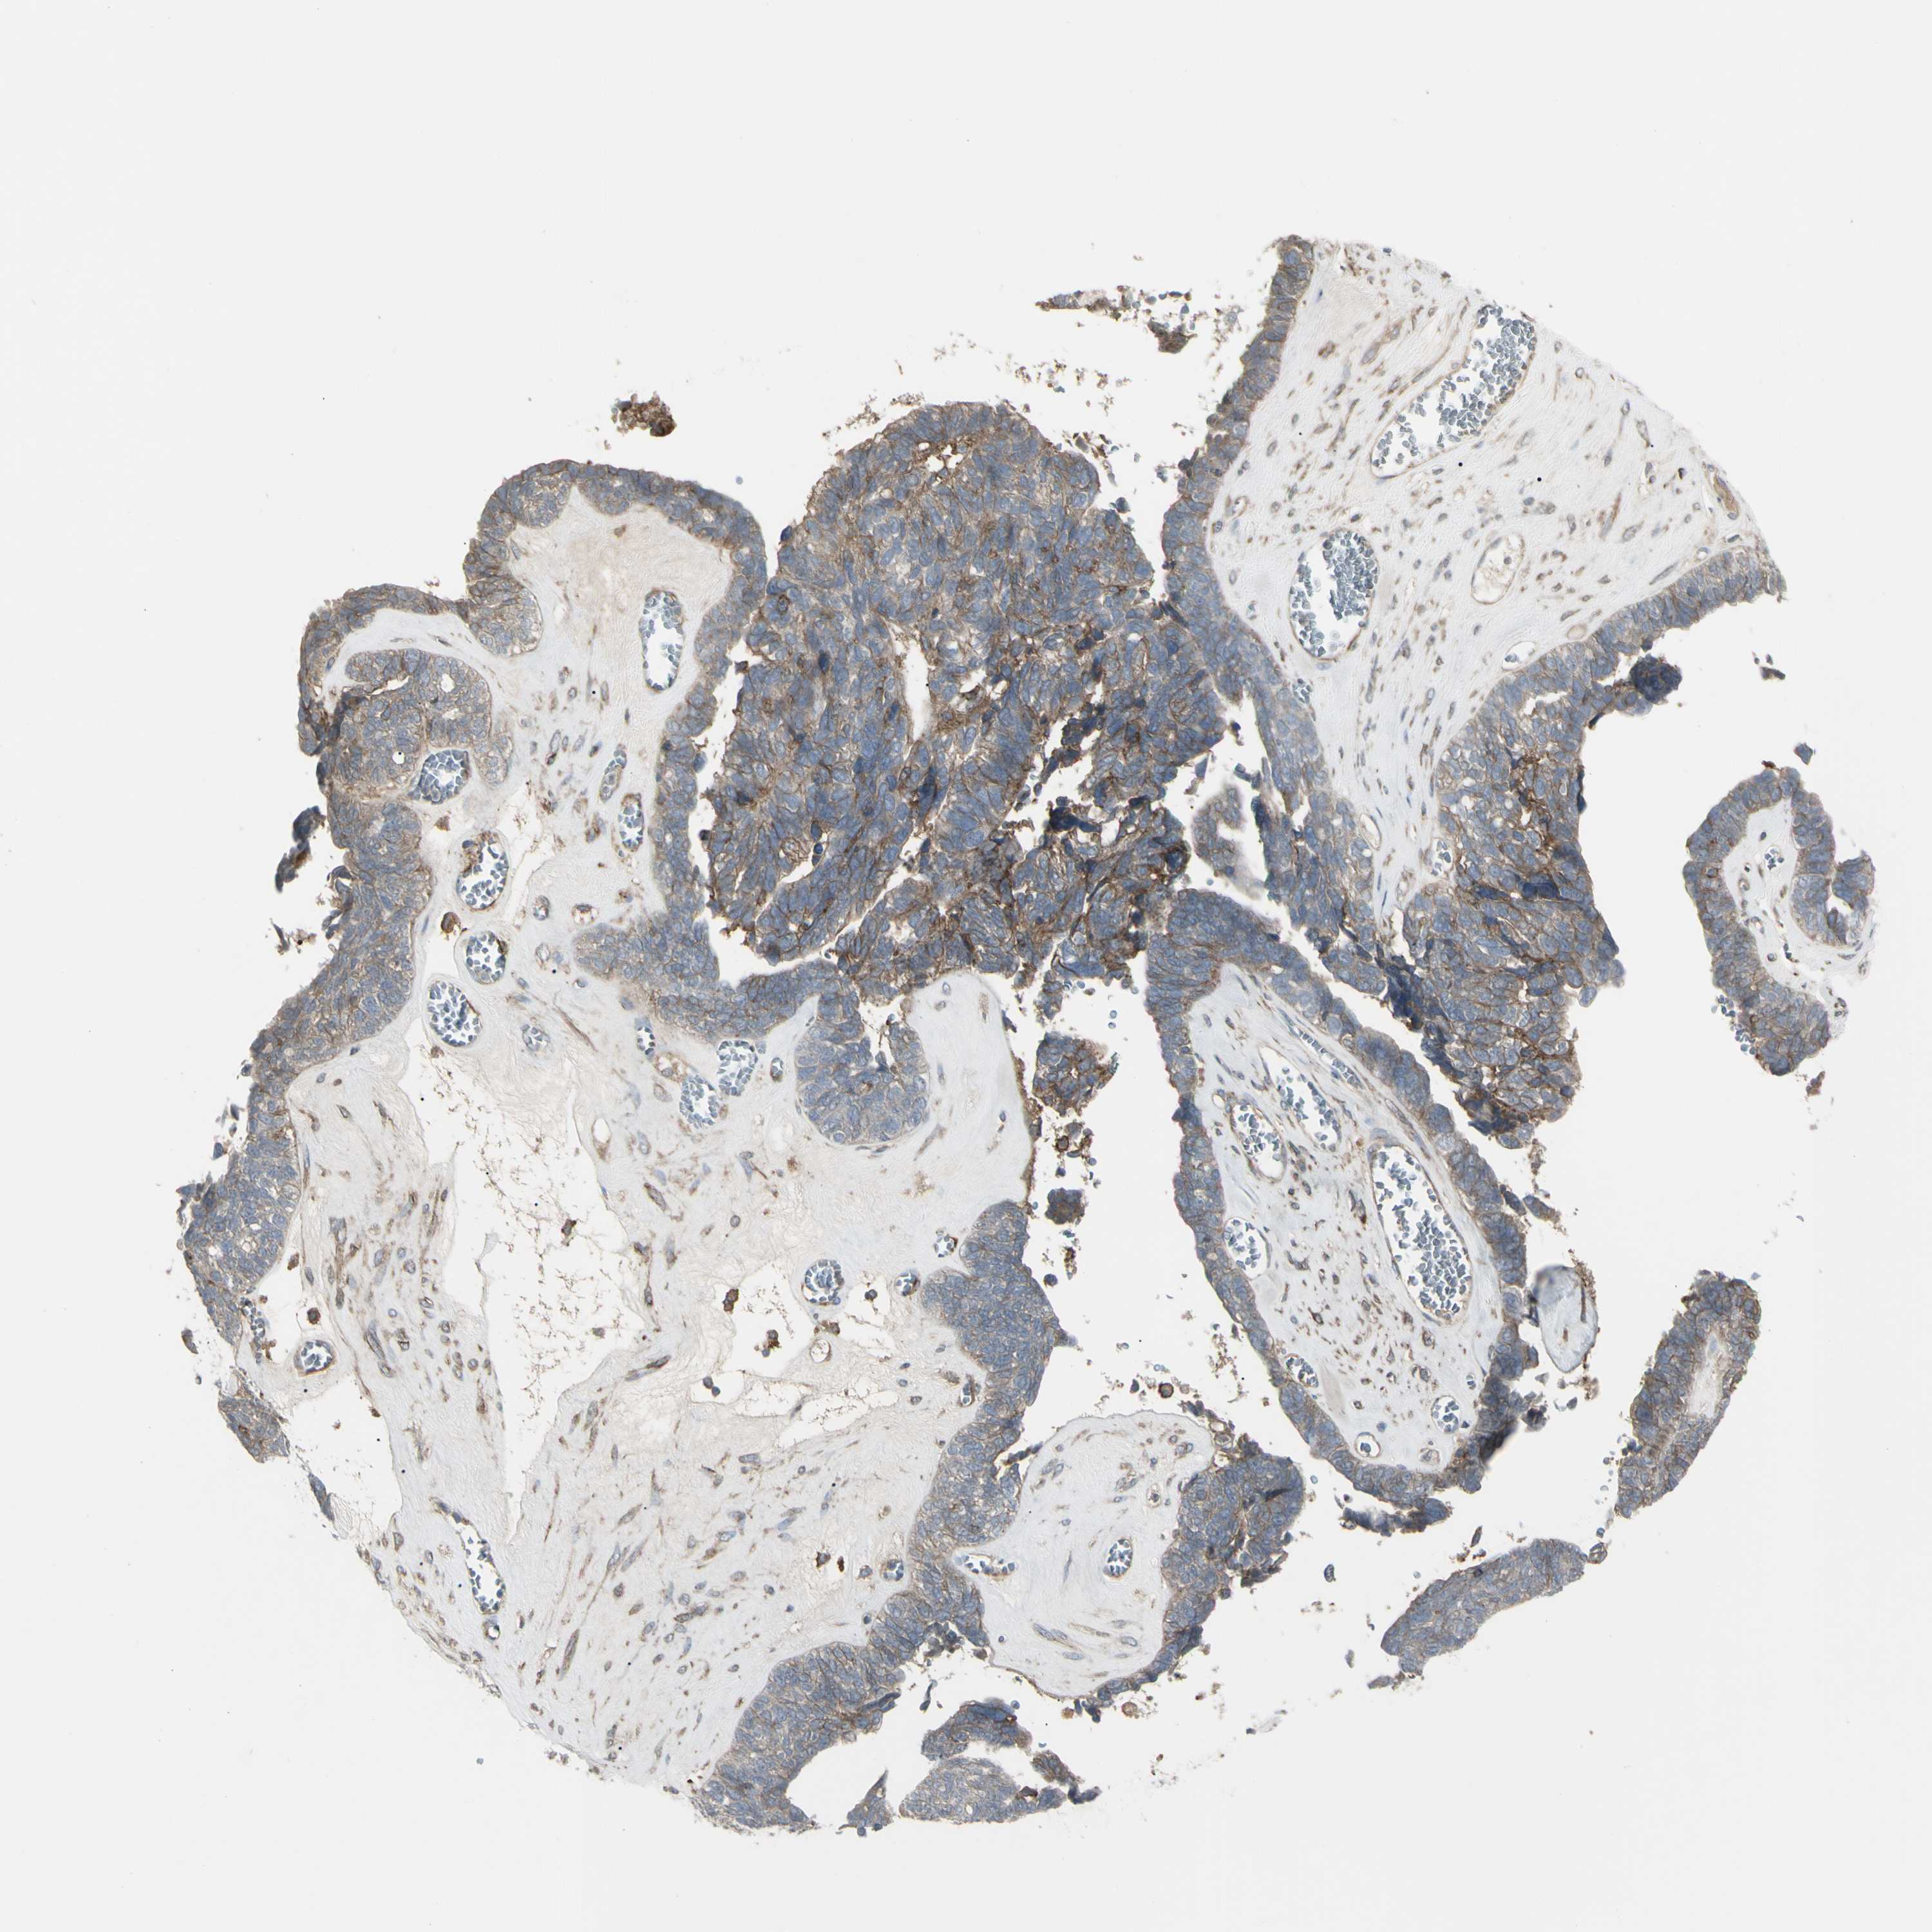

OVARIAN CANCER - Protein expressioni

A mouse-over function shows sample information and annotation data. Click on an image to view it in a full screen mode. Samples can be filtered based on level of antibody staining by selecting one or several of the following categories: high, medium, low and not detected. The assay and annotation is described here.

Note that samples used for immunohistochemistry by the Human Protein Atlas do not correspond to samples in the TCGA dataset.

Antibody stainingi

Antibody staining in the annotated cell types in the current human tissue is reported as not detected, low, medium, or high, based on conventional immunohistochemistry profiling in selected tissues. This score is based on the combination of the staining intensity and fraction of stained cells.

Each image is clickable and will lead to virtual microscopy that enables deeper exploration of all samples and also displays staining intensity scores, fraction scores and subcellular localization as well as patient and tissue information for each sample.

Antibody HPA009285

Antibody HPA017139

Antibody CAB017826

Cystadenocarcinoma, serous, NOS

Carcinoma, endometroid

Cystadenocarcinoma, mucinous, NOS

Carcinoma, NOS